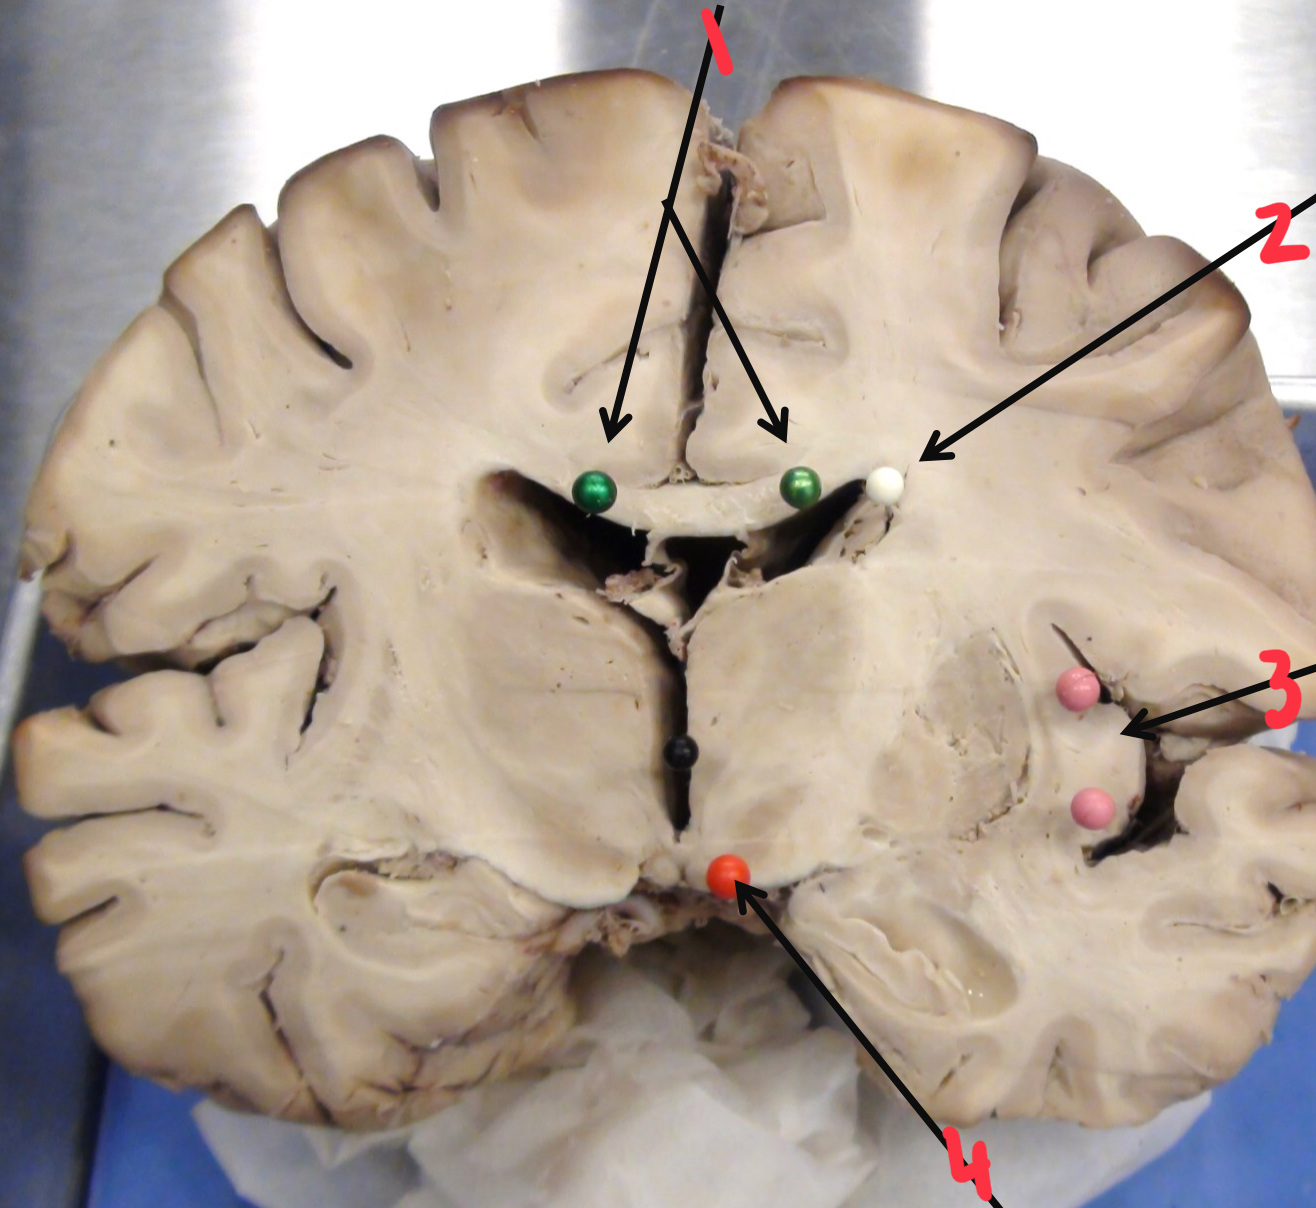

1

choroid plexus

2

pineal gland

3

lenticular (lentiform) nucleus

4

thalamus

5

internal capsule

6

septum pellucidum